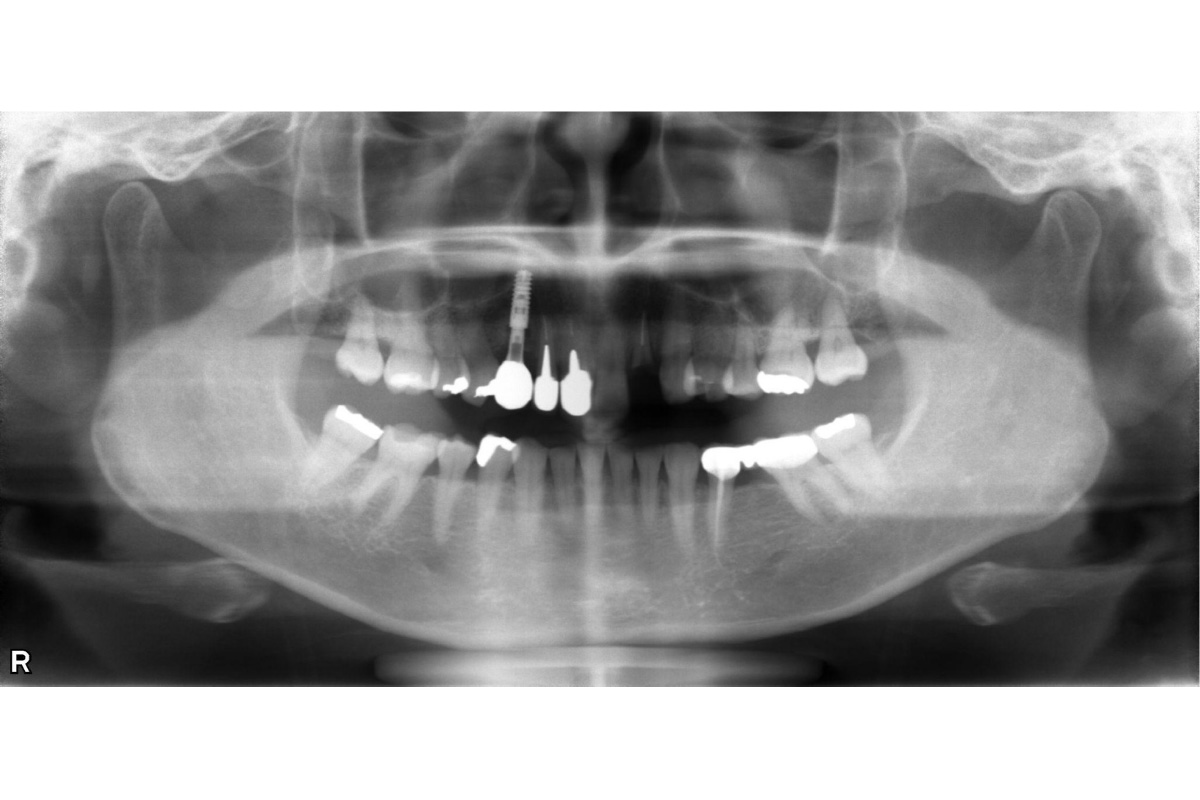

治療前